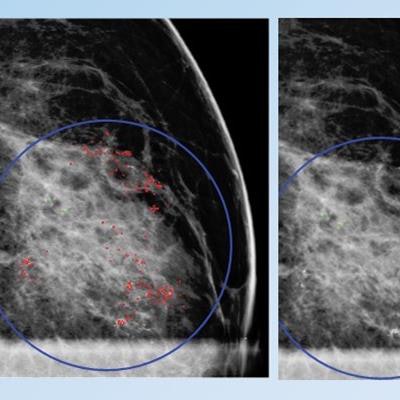

False positive for radiologist and true negative for qCAD. Fine linear branching and rim calcifications measuring 7 cm with regional distribution in the middle lateral region: path-proven fat necrosis.

False positive for radiologist and true negative for qCAD. Fine linear branching and rim calcifications measuring 7 cm with regional distribution in the middle lateral region: path-proven fat necrosis.With deep-learning training, the CAD software can recognize and eliminate benign lesions, she said.

"This dramatically reduces most false markings, which are a nuisance and distraction for mammographers," she said.